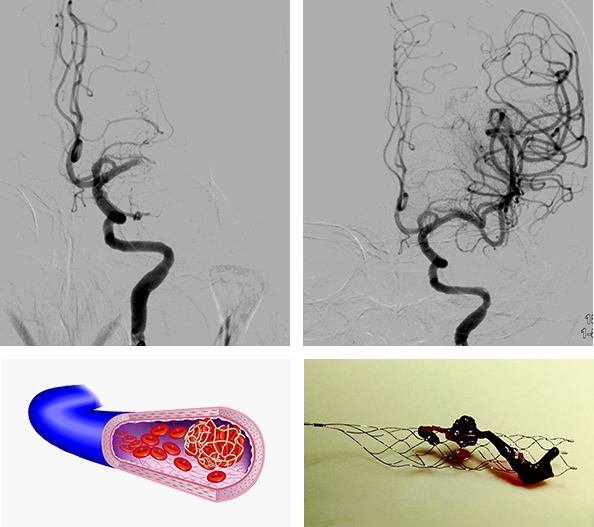

1. 코일 색전술

- 뇌동맥류 색전술은 뇌동맥류 출혈이 발생했거나 앞으로 생길 수 있는 출혈 예방을 위해 뇌동맥류를 정상 혈류로부터 완전히 차단하는 치료방법으로, 동맥류 속에 미세도관을 삽입하고 백금으로 만든 코일을 채워 넣어 정상혈관을 침범하지 않도록 하는 방법입니다.

3. 경동맥 풍선 확장술 및 뇌혈관 스텐트 삽입술

<경동맥 풍선 확장술 및 뇌혈관 스텐트 삽입술>

- 신경중재(neurointervention)라는 용어는 다양한 신경계 질환을 두개골이나 척추골 절개 없이 영상 유도(image guidance)하에서 경피적으로 접근하여 치료하는 행위를 말하며, 뇌혈관에서도 동맥경화 등에 의한 협착증이 있을 경우 임상 양상을 고려하여 좁아진 혈관을 넓혀 주기 위해 풍선도관(balloon catheter)을 이용한 혈관성형술을 하거나 필요한 경우 스텐트 삽입술을 실시하고 있습니다.

<경동맥 풍선 확장술 및 뇌혈관 스텐트 삽입술>